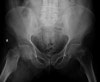

X-ray : 전자하 골절(Subtrochanteric fracture)